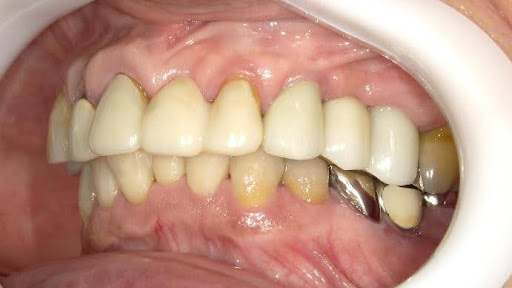

Before

枚方市のインプラントの症例

After

M・I 様 女性 70代

症状としては、左下56は、歯周病で欠損したと考えられるが、かなりの骨欠損をともなっていた。左上456に関しては、動揺が大きく、炎症が起き、排膿、および、歯性上顎洞炎を起こしていた。

治療法としては、動揺がひどくなってきて、炎症の症状もあったため、左上56の抜歯を希望。インプラント治療をその後、希望したため、左上4に関しては抜歯即時埋入。左上6に関しては、既存骨1から2mmでインプラント治療が厳しい状態であったが、グラフトレスサイナスリフトを行い、治療期間5か月はかかるということを説明して、インプラント埋入をおこないました。その後、2か月半後、大幅に骨が欠損している下顎56に対して、ショートインプラントを使用して、下顎神経の損傷を避けて、インプラント埋入を終えています。その後2か月後に光学印象で印象を行い、上顎刺億456歯、3ユニットのジルコニアブリッジを装着。下顎左側56に関しては、骨欠損が大きいため、歯冠長がだいぶ長くなるため、ジルコニアの連結冠を装着して治療を終えた。

治療結果は、上顎6に関しては、既存骨が少なく、厳しい治療ではありましたが、5か月で治療を終え、患者様の負担を最小限に抑えるができたと考えます。(従来のサイナスリフトでは、このようなケースでは1年以上、1年程度の治療期間がかかるか、治療が不可能と言われるケースだと考えます。)また、下顎は骨欠損が大きく、下歯槽管のリスクが起きることが考えられますが、ショートインプラントを使用することで安全に治療を行うことができました。

治療の期間・回数:治療期間5か月(上顎456 3ピースブリッジの治療は5か月(上顎既存骨が2mm程度しかなく、骨結合に時間がかかるケースであったために、5か月の治療期間が必要であった。)(左下56に関しては2か月半で治療を終えています。)治療回数は、13回。

治療の価格:1,474,000円(税込)

治療費の内訳:左上46および左下56のインプラント基本料(フィックスチャー及び手術費用、投薬費用、レントゲン費用、インプラント上部費用(アバットメントおよびジルコニアクラウンの費用用)330000円(税込み)×4本分 1320000円(税込)。左上5ジルコニアポンテック費用88000円(税込)。オプション費用、左上4抜歯即時埋入加算(人工骨費用を含む)+グラフトレスサイナスリフト費用 33000円(税込)、左上6グラフトレスサイナスリフト費用 33000円(税込)

治療のリスクや副作用:手術後に、痛みや腫れ、出血、合併症などを引き起こす可能性があります。噛む感覚がご自身の歯と異なる場合があります。見た目がご自身の歯と異なる場合があります。手術後にメインテナンスを継続しないと、インプラントが抜け落ちる可能性があります。